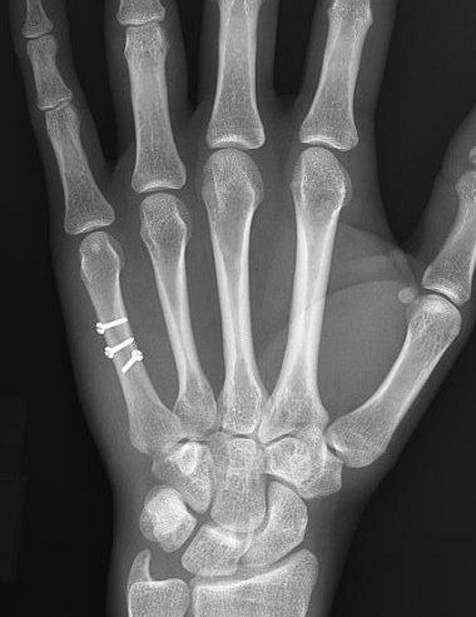

3-1: مقدمه: هر انگشت دست از طریق یک استخوان متاکارپ به مچ دست متصل میشود که شکستگی های این پنج استخوان در کف دست شایع بوده و در همه سنین دیده میشوند. این استخوان ها به شکل مدادهای کوتاهی هستند. قسمتی از این استخوان ها که با انگشت مفصل میشود برجسته و گرد شده است. به این قسمت سر استخوان متاکارپ میگویند. وسط استخوان متاکارپ را تنه آن مینامند و بین سر و تنه را گردن استخوان متاکارپ نامگذاری کرده اند.

2-3: مکانیسم شکستگی متاکارپ ها: شایعترین علت این شکستگی ها زمین خوردن یا ضربه مستقیم به پشت دست یا مشت زدن است. این شکستگی ها معمولا عرضی و بدون جابجایی هستند ولی ممکن است مایل یا مارپیچی بوده و یا با جابجایی همراه باشند.

3-3: علائم وتشخیص شکستگی متاکارپ های کف دست: بدنبال شکستگی پشت دست متورم و دردناک شده و فشار به محل شکسته شده شدت درد را افزایش میدهد. پوست روی استخوان شکسته ممکن است کبود شود. مشت کردن دست معمولا شدت درد را افزایش میدهد. تشخیص این شکستگی ها با رادیوگرافی ساده است.

3-4 : درمان شکستگی های متاکارپ: در شکستگی های بدون جابجایی یا با جابجایی اندک، تنها درمان مورد نیاز استفاده از یک آتل برای بیحرکت کردن محل شکستگی و کاهش درد است. در مواردیکه جابجایی قطعات شکسته شده زیاد باشد درمان بصورت جااندازی بسته و گچ گیری است. در مواردی که شکستگی بعد از جااندازی ناپایدار باشد پزشک معالج با استفاده از پین های فلزی که آنها را از طریق پوست به داخل استخوان و محل شکستگی هدایت میکند، قطعات شکسته شده را به یکدیگر متصل میکند. در مواردی که جااندازی بسته موفقیت آمیز نباشد پزشک معالج اقدام به جااندازی باز شکستگی و فیکس کردن قطعات شکسته شده بوسیله پین یا پیچ و پلاک میکند.